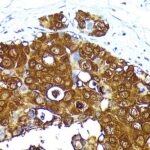

Immunohistochemistry analysis of paraffin-embedded human breast cancer using Mammaglobin A Rabbit mAb (A19727) at dilution of 1:200 (40x lens).Perform high pressure antigen retrieval with 10 mM Tris/EDTA buffer pH 9.0 before commencing with IHC staining protocol.